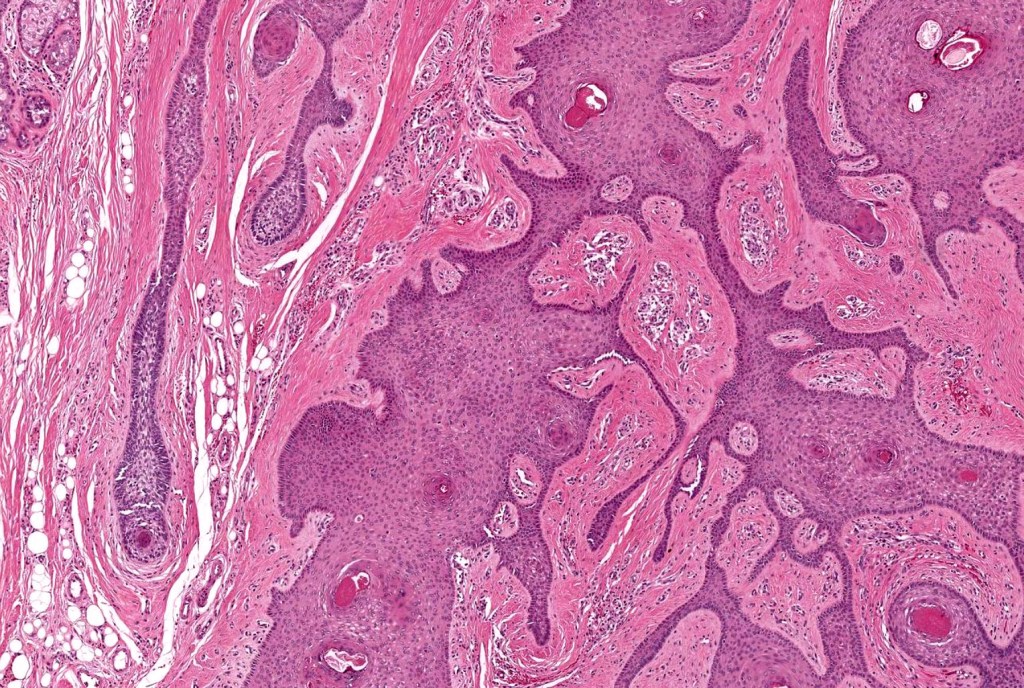

•Circumscribed dermal nodule with a characteristic silhouette

•An infundibular cyst is surrounded by laminated dermal collagen, elastic fibers, blood vessels, adipocytes & spindle cells separated from the adjacent dermis by a retraction artifact

•The cyst contains keratinous debris, and its wall shows conspicuous sebaceous & sometimes hair follicular elements are also evident

Folliculosebaceous cystic hamartoma can be distinguished from trichofolliculoma/sebaceous trichofolliculoma by the striking connective component and retraction artifact.